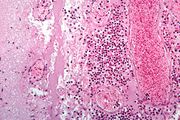

| 04:03, 21 August 2013 | IPLab10Candidiasis5.jpg (file) | 91 KB | This higher-power photomicrograph shows the yeasts and pseudohyphae in this focus of Candida organisms. | 1 | |